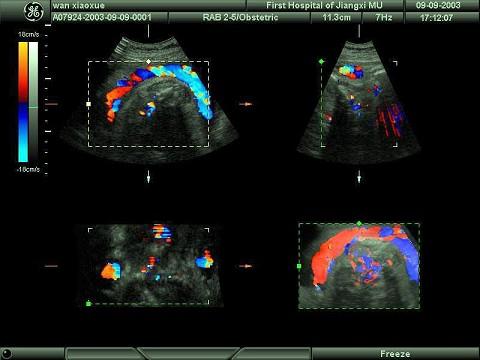

某孕妇胎儿颈部可探及下列图像,最可能的诊断为?(?)A.脐带绕颈B.胎盘早剥C.先天畸形D.正常结构E.脐带搭颈

问题 某孕妇胎儿颈部可探及下列图像,最可能的诊断为?(?)

选项 A.脐带绕颈 B.胎盘早剥 C.先天畸形 D.正常结构 E.脐带搭颈

答案 A